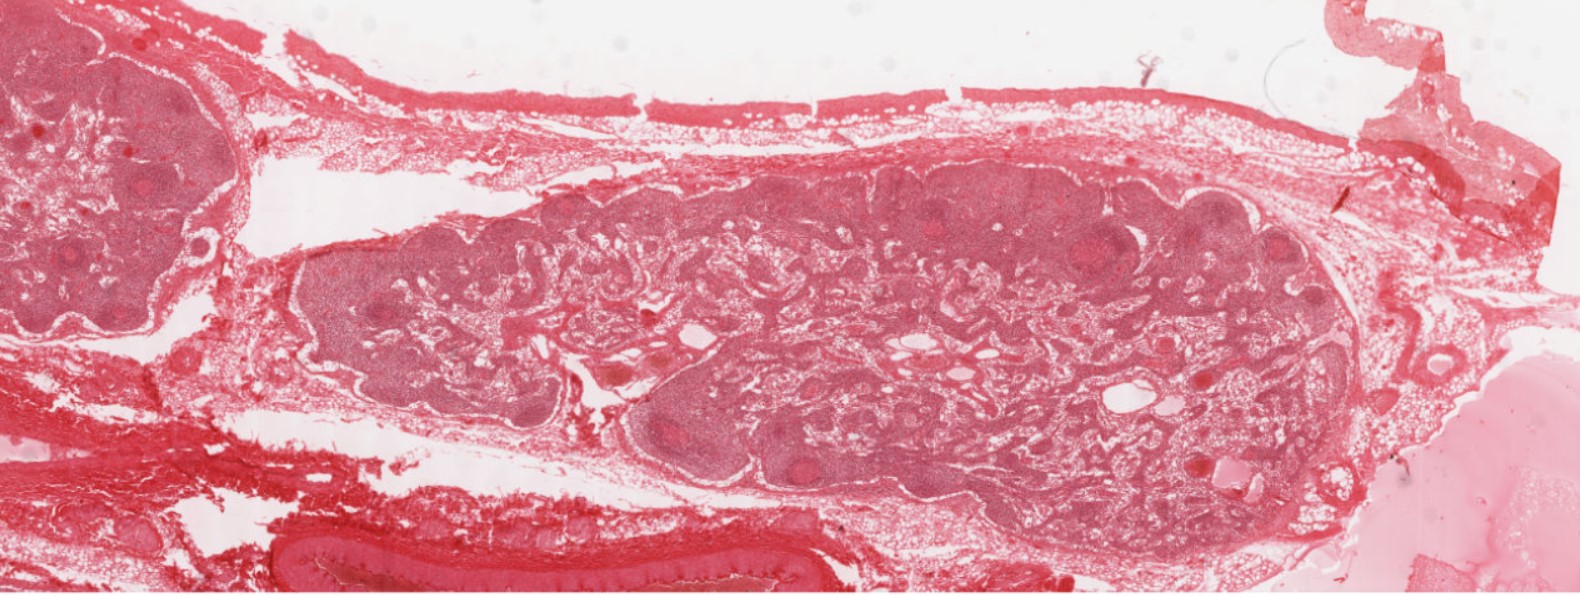

Image Link: https://histologyslides.med.umich.edu/Histology/Basic%20Tissues/Muscle/058thin_HISTO_83X.htm